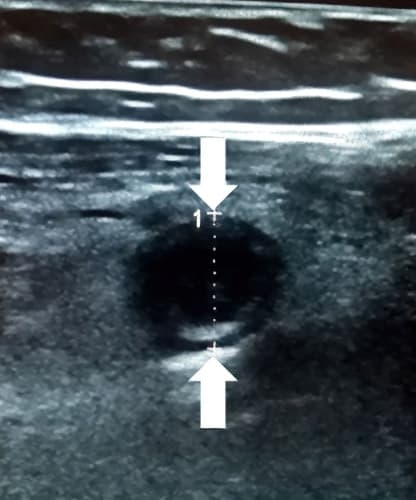

При поперечном сканировании напоминает «мишень»: внутреннее гиперэхогенное кольцо отображает воспаленный и отечный подслизистый слой; наружное гипоэхогенное (или анэхогенное) кольцо отображает воспаленный и отечный мышечный слой (см. рис. 2, 2а).

Рисунки 2, 2а. При поперечном сканировании аппендикс имеет вид «мишени».

Аппендикс считается расширенным, если под действием компрессии его наружный переднезадний размер, измеренный при поперечном сканировании, более 6 мм (см. рис. 3).

Рисунок 3. Определение диаметра аппендикса.